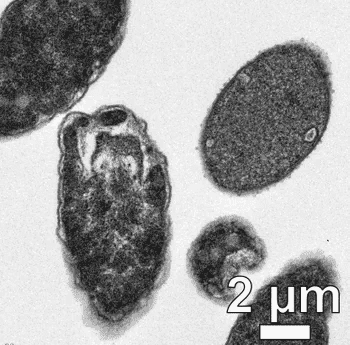

它们的工作原理是附着在细菌细胞表面。当暴露在光线下时,它们会快速旋转,直接在细菌中钻孔。周三发表在同行评审期刊《科学进展》(Science Advances)上的一篇论文描述了这项新技术。

这种钻头通过在膜上钻洞并打开来杀死细菌。

这种钻头通过一种机制杀死细菌,这种机制几乎不可能被细菌防御,因为这是一种机械作用,而不是化学作用。